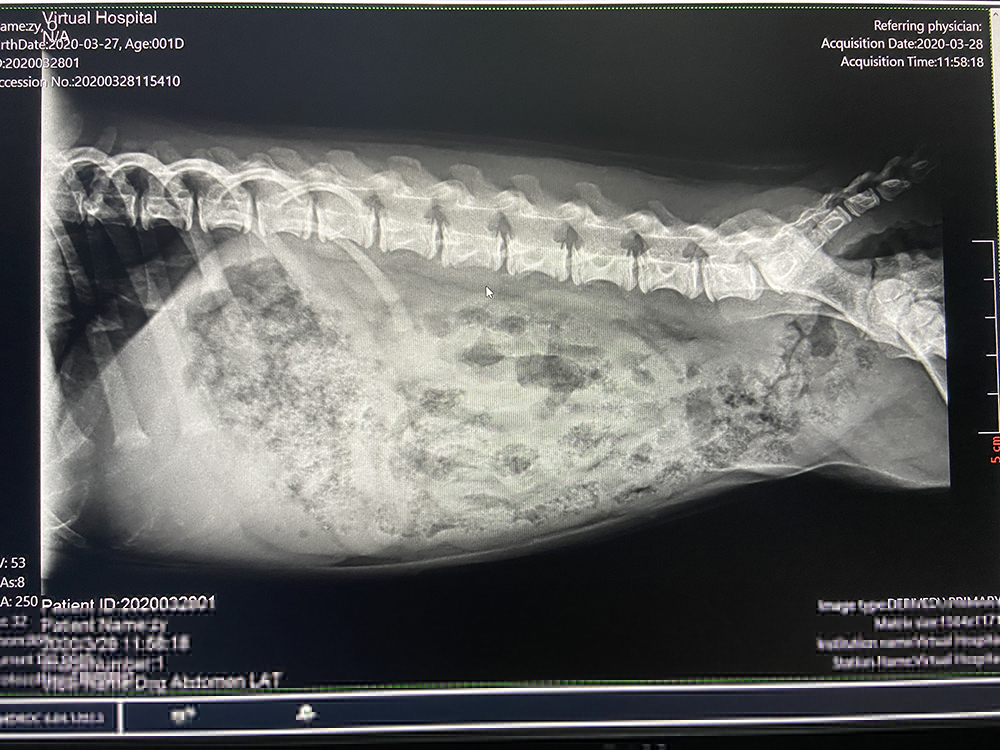

連云港凱睿寵物診所

2020/4/24